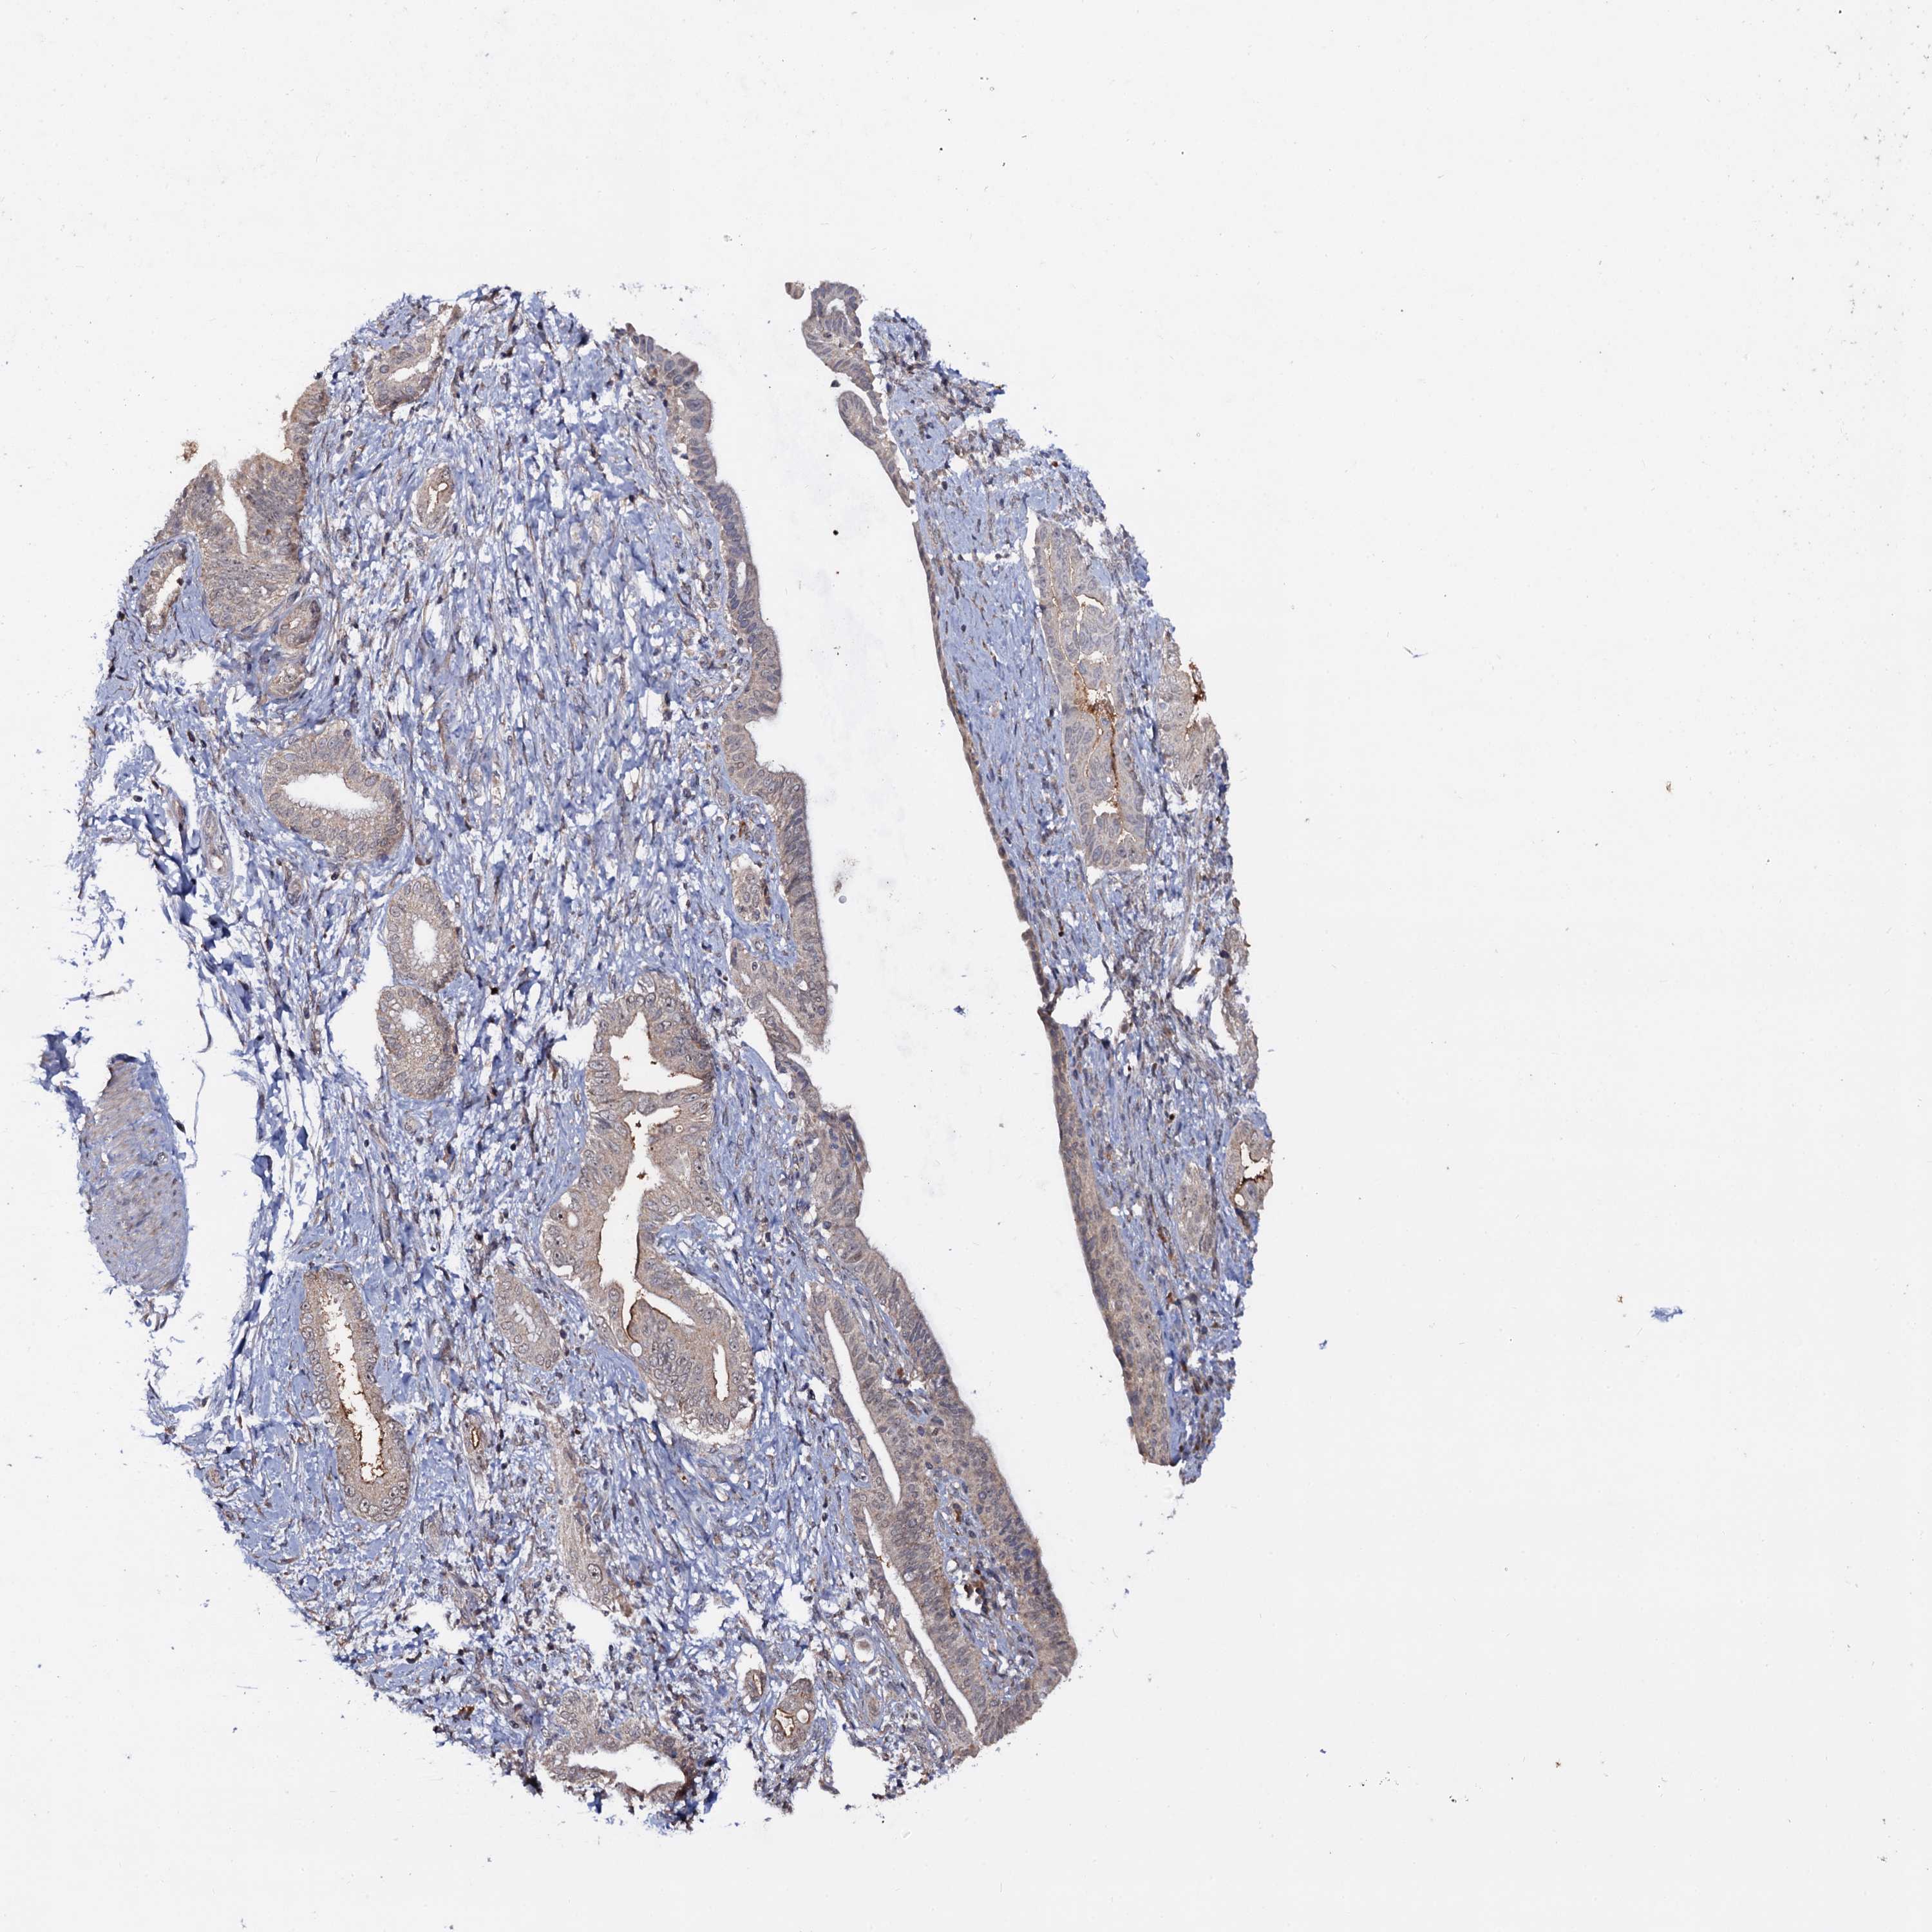

PANCREATIC CANCER - Protein expressioni

A mouse-over function shows sample information and annotation data. Click on an image to view it in a full screen mode. Samples can be filtered based on level of antibody staining by selecting one or several of the following categories: high, medium, low and not detected. The assay and annotation is described here.

Note that samples used for immunohistochemistry by the Human Protein Atlas do not correspond to samples in the TCGA dataset.

Antibody stainingi

Antibody staining in the annotated cell types in the current human tissue is reported as not detected, low, medium, or high, based on conventional immunohistochemistry profiling in selected tissues. This score is based on the combination of the staining intensity and fraction of stained cells.

Each image is clickable and will lead to virtual microscopy that enables deeper exploration of all samples and also displays staining intensity scores, fraction scores and subcellular localization as well as patient and tissue information for each sample.

Antibody HPA039318

Antibody HPA039763

Adenocarcinoma, NOS